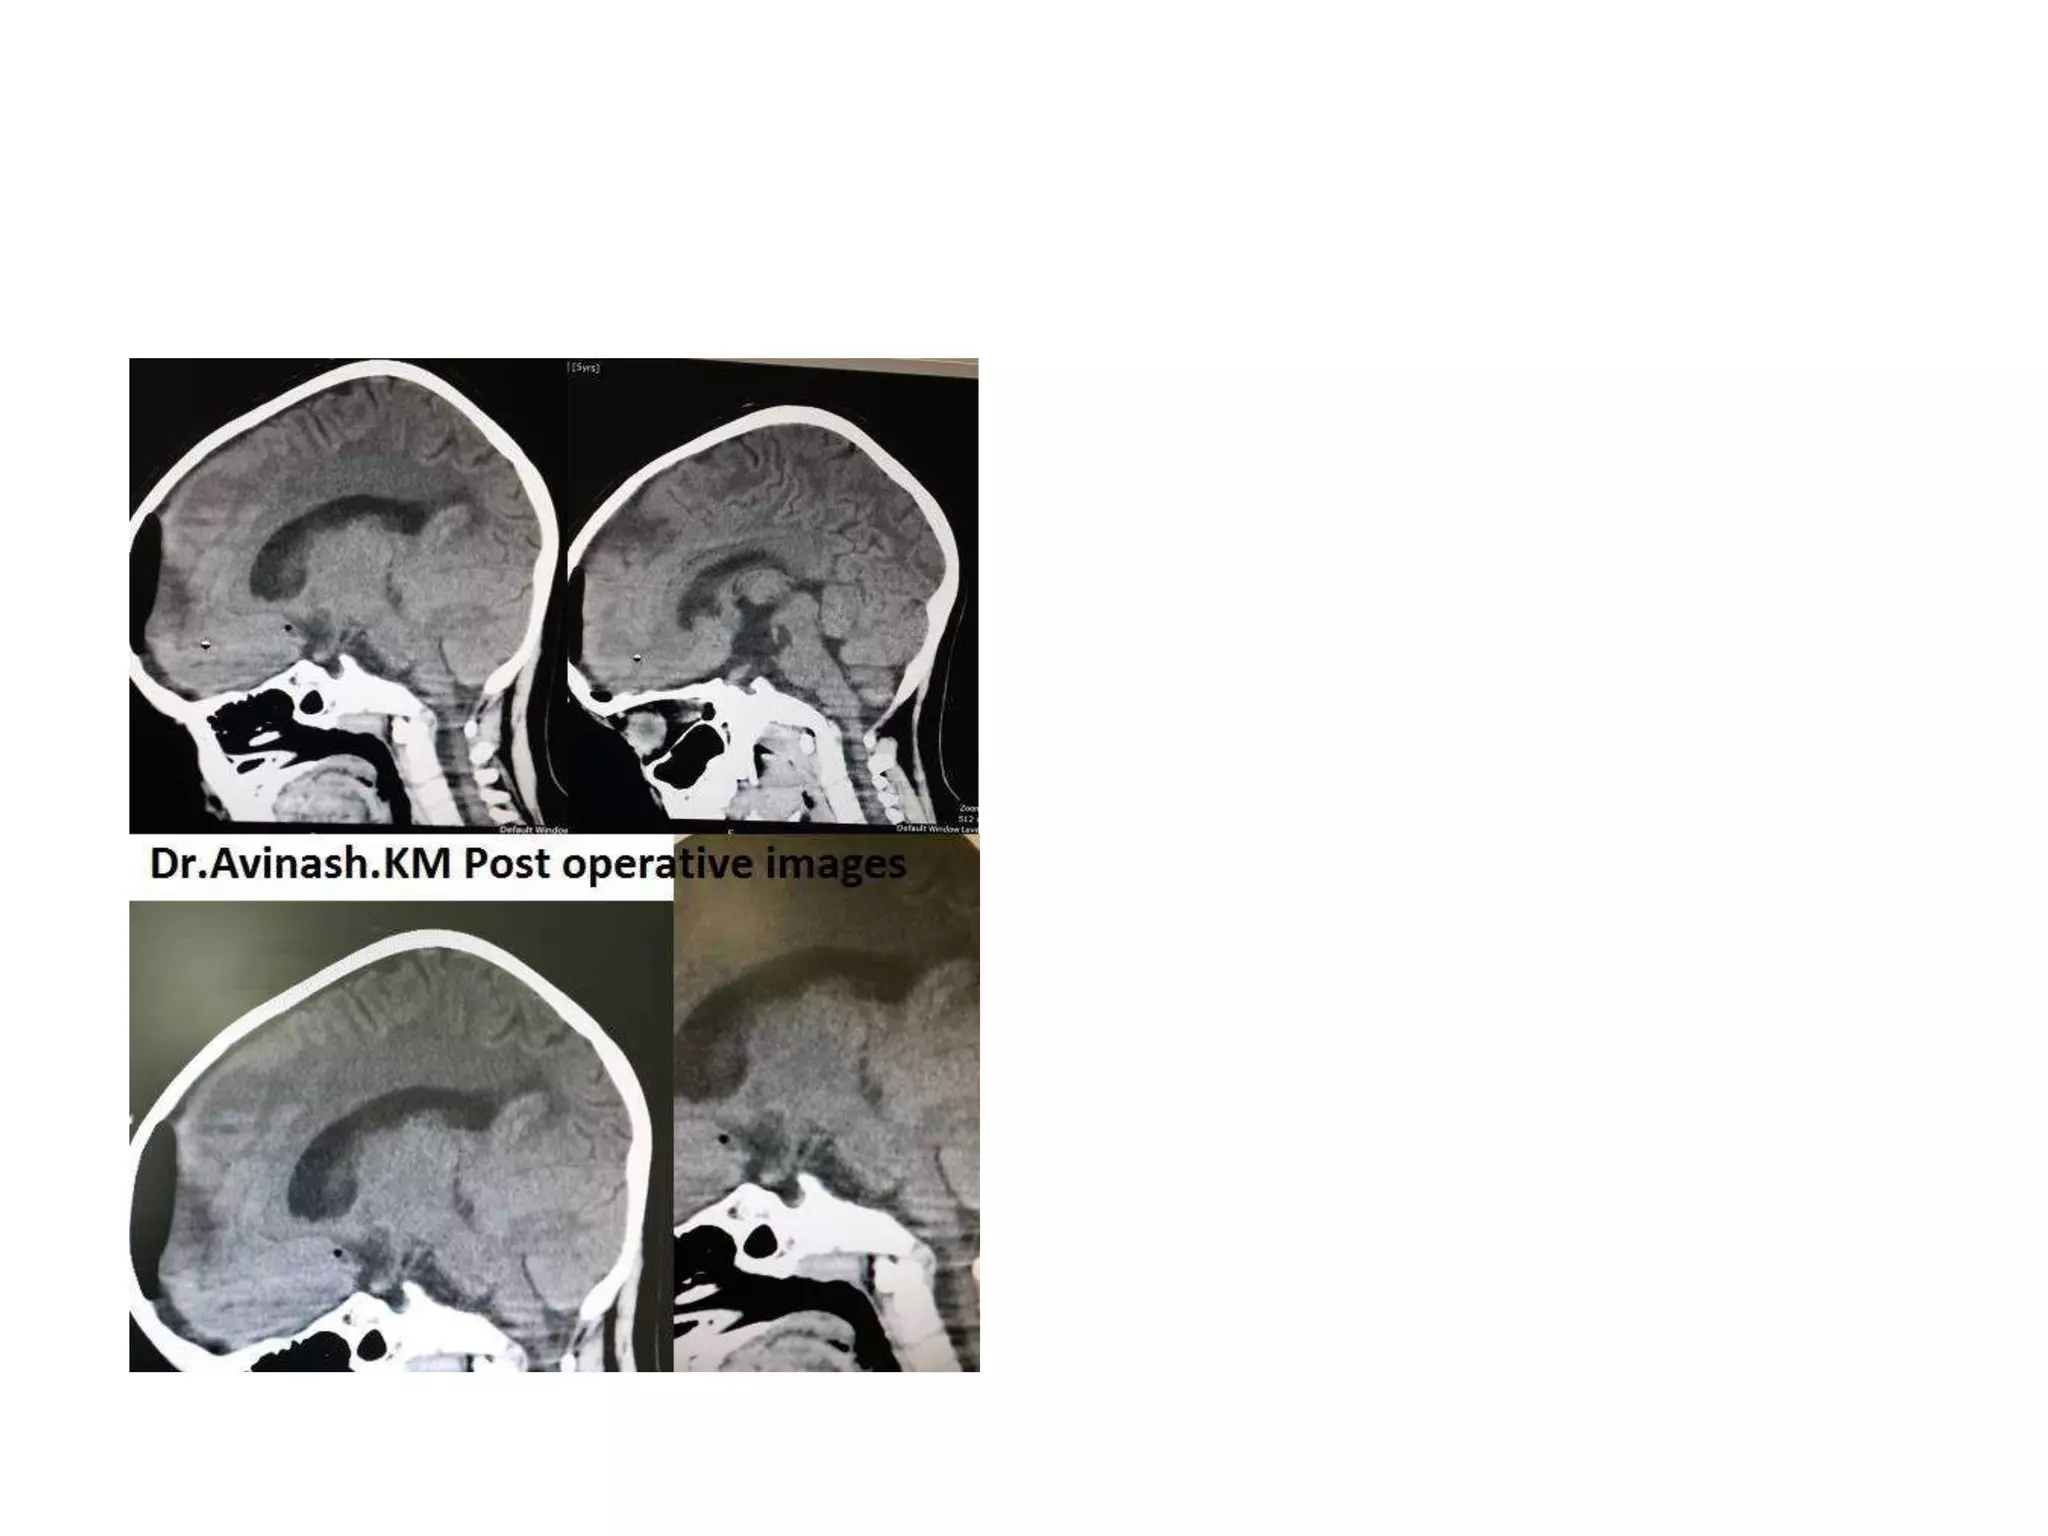

In anterior skull base approach - Type C Modified

Transcochlear Approach – after cutting the tentorium

With mild retraction of the temporal lobe, the bifurcation of the internal carotid artery (ICA) into

the anterior (ACA) and middle cerebral (MCA) arteries is seen. The ipsilateral (ON) and

contralateral (ONc) optic nerves are seen. The oculomotor nerve (III) is embraced by the

posterior cerebral artery (PCA) superiorly and the superior cerebellar artery (SCA) inferiorly

http://www.ajnr.org/content/27/8/1770/F2.expansion.html